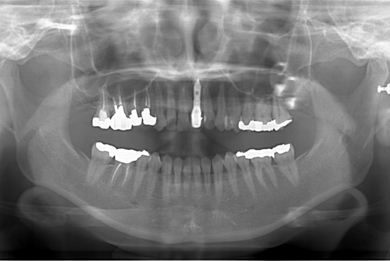

抜歯即日スピードインプラント治療

| 性別/年齢 | 女性 / 39歳 | ||||||||||||||||||||||||||||||||

| 主訴 | 左前歯の虫歯治療を希望。 | ||||||||||||||||||||||||||||||||

| 治療内容 | インプラント1本(抜歯即日スピードインプラント)、メタルボンドセラミック1本 | ||||||||||||||||||||||||||||||||

| 総治療費 | 458,588円 | ||||||||||||||||||||||||||||||||

| 治療期間 | 1年0ヶ月 |